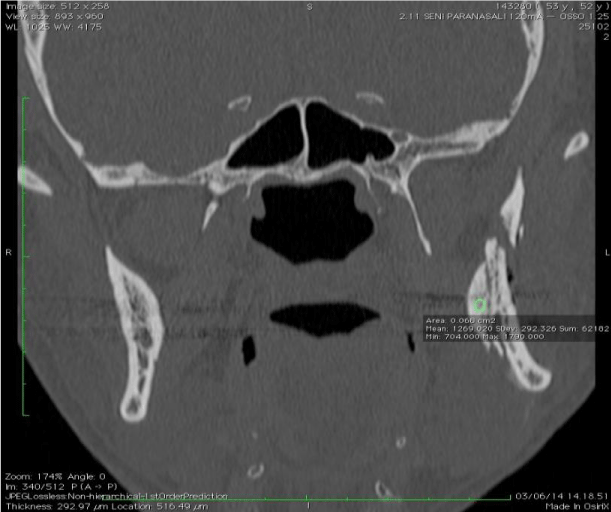

Figure 9:

Volume rendering illustrating double bad split and osteosynthetic material in situ.